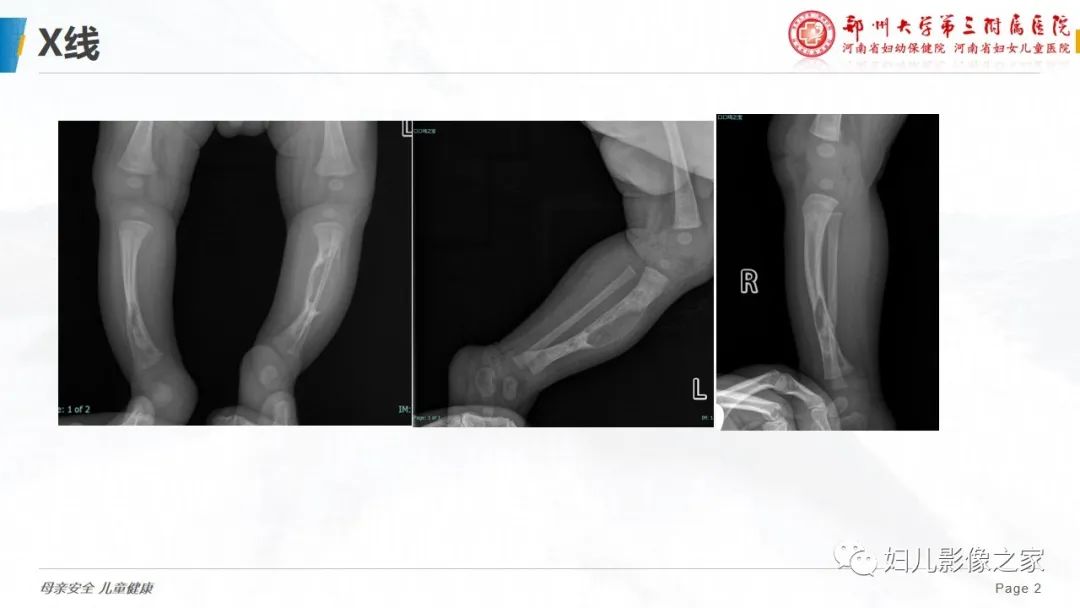

【PPT】骨纤维结构不良-2